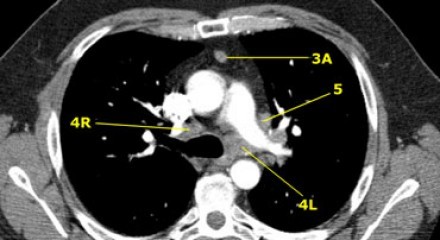

4R. Paratraqueais Inferiores Direitos

Limite superior: intersecção da margem caudal da veia inominada (brachiocefálica esquerda) com a traqueia.

Limite inferior: borda inferior da veia ázigo.

Linfonodos 4R estendem-se para a borda lateral esquerda da traqueia.

5. Linfonodos Subaórticos